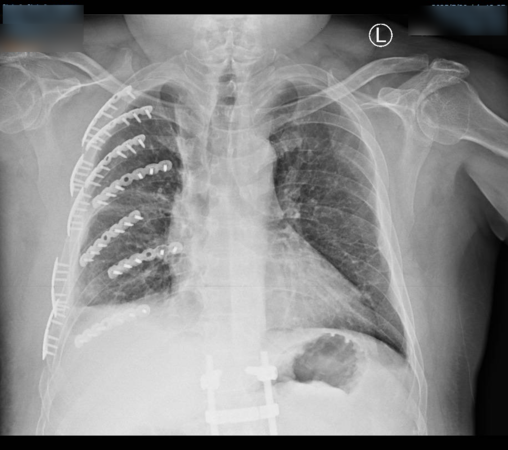

送醫後檢查發現,陳男不僅有8根肋骨斷成14截,更出現致命性的「連枷胸」,吸氣時胸腔會反常凹陷;右手橈骨粉碎性骨折碎成10多塊,骨盆腔也嚴重受損。

彰化醫院胸腔創傷中心主任林聿騰指出,透過3D胸廓重組影像定位,僅開2個小傷口就用鈦合金骨板固定變形胸腔。骨科醫師陳柏辰接力以鋼板處理粉碎的右手橈骨。歷經馬拉松式手術,陳男總算脫離痛苦。歷經接連手術後,已轉到一般病房,在家人照顧下的他說,手術前,再強的止痛劑也無法止痛,經微創手術後,他才體會到可以自由呼吸是多麼美好的事。